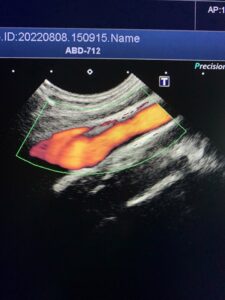

↑↑上の写真は、血管のようなチューブ状のものが見る方向によってどう見えるか?の例です。

←そしてこれが同じ血管の縦断面。

※わかりやすく、血管を赤く色づけしています。